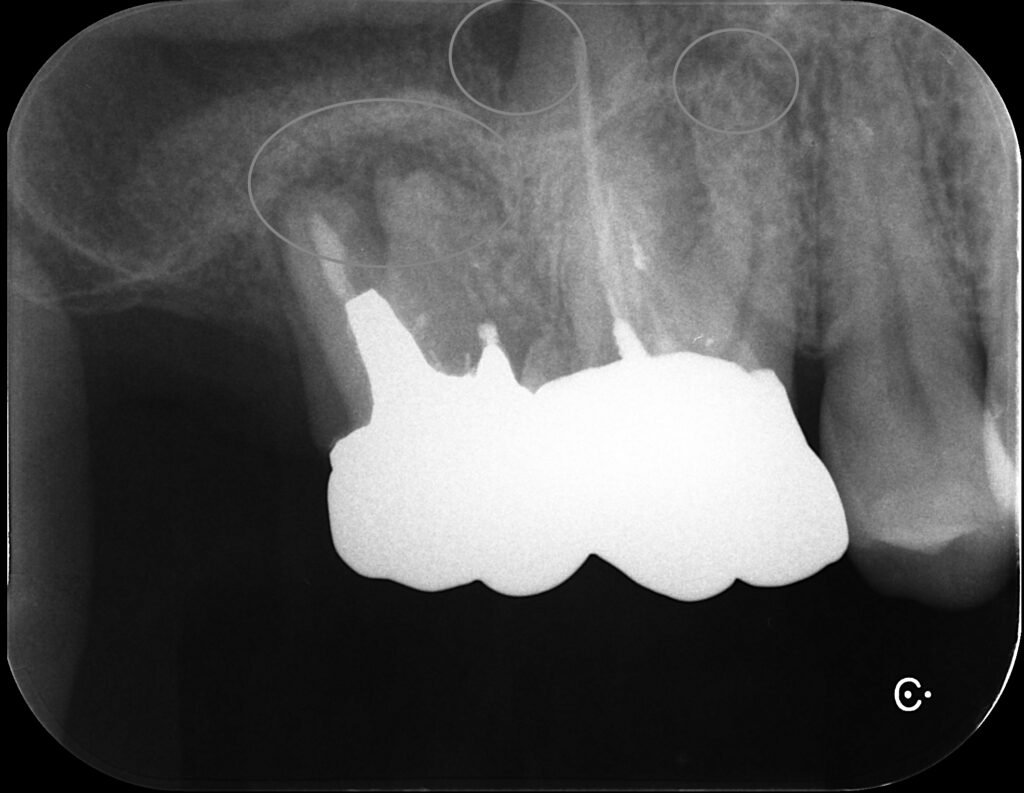

クラウンを除去、何回か根管を洗浄し様子を見ます。

洗浄している最中の写真

(コア外すの大変だった‥)

右側の写真は6番根管充填後。GP使用。

その後7番(一番左)も根充し、クラウンSET。